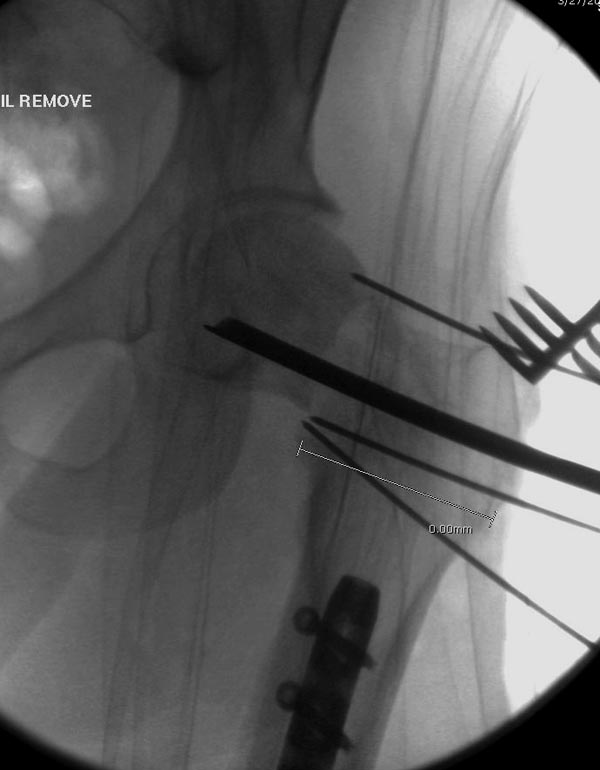

Здесь выставлен ренгенограммы больного, ему 21, травму получил в

результате высокоскоростной погони на украденной машине, которая

закончилась смертью трех остальных“боевых комрадов”. Начатую коллегой

открытую операцию на шейке пришлось закончить мне, установкой винтов и

ретроградной фиксацией бедра. Выписка в обычное сроки и наблюдался